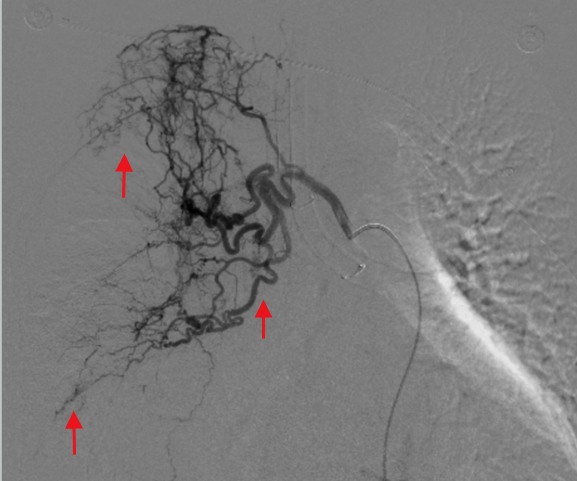

手术过程中,医疗团队规范操作。术中造影清晰显示,患者右侧支气管动脉存在明显扩张迂曲畸形,且有广泛明显的造影剂外渗出血影。随后,医生小心操作,将超选导管送至右侧出血动脉主干,采用1个44mm规格、1个43.7mm规格弹簧圈进行动脉栓塞,再运用适量明胶海绵颗粒进一步栓塞支气管动脉,直至血流停滞。再次造影确认出血影完全消失,左侧肺支气管动脉未见异常。整个手术过程顺利,术后患者恢复良好,症状平稳,最终康复出院。

▲术中造影见右肺支气管动脉迂曲畸形,可见广泛明显造影剂外渗出血影